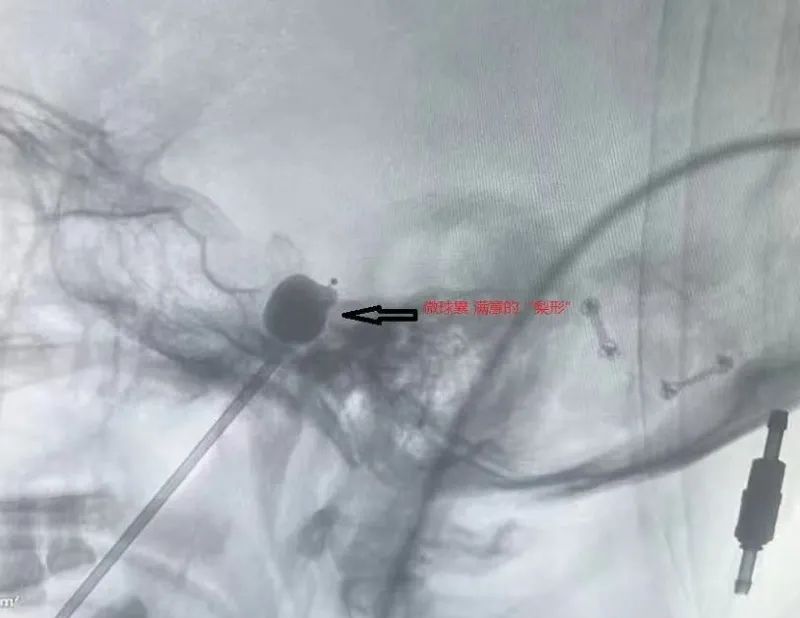

將球囊置入到三叉神經半月節(jié)位置

再將造影劑注入球囊中

待球囊擴張呈梨形后

精準壓迫引起疼痛的神經

完成后拔出穿刺針及球囊導管

手術很順利

僅用時20分鐘